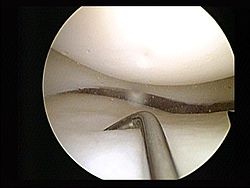

Lancet. 24 de septiembre de 2018InterpretaciónEn general, el riesgo asociado con someterse a una meniscectomía parcial artroscópica fue bajo. Sin embargo, algunas complicaciones poco frecuentes pero graves (que incluyen embolia pulmonar e infección) están asociadas con el procedimiento y los riesgos no han disminuido con el tiempo. En vista de la incertidumbre sobre la efectividad de la meniscectomía parcial artroscópica, una apreciación de los riesgos relativos es crucial para los pacientes y los médicos. Nuestros datos proporcionan una base para la toma de decisiones y el consentimiento.